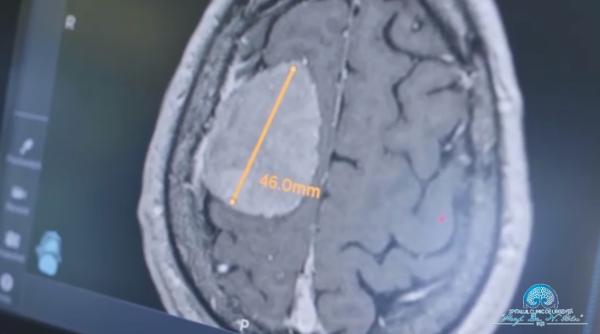

Tumoră cerebrală de mari dimensiuni, operată cu succes de medicii de la Spitalul "Prof. Dr. Nicolae Oblu" din Iaşi 10 Ianuarie 2024